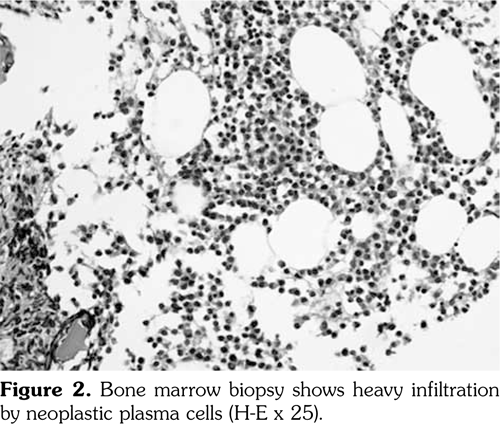

Two years later, the patient presented with an ulcer on the left nasolabial groove. Skin biopsy of the affected tissue revealed damaged epidermis with basal-cell carcinoma infiltration in the dermis (Figure 1), suggesting basal-cell carcinoma for which she underwent a resection. There were no clinical or laboratory signs suggestive of DM activity.